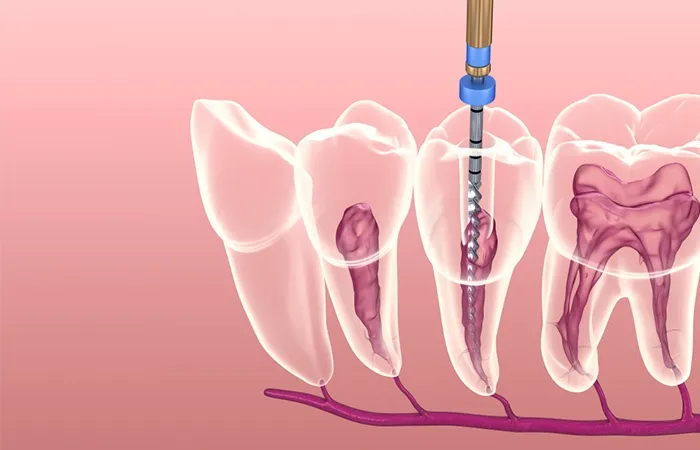

Hàn ống tủy răng là kỹ thuật nha khoa được nha sĩ chỉ định trong các trường hợp răng gặp vấn đề hoặc bệnh lý liên quan